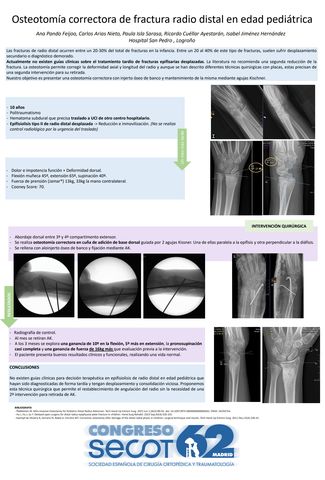

Osteotomía correctora de fractura radio distal en edad pediátrica

ANA PANDO FEIJOO, CARLOS ARIAS NIETO, PAULA ISLA SARASA, RICARDO CUÉLLAR AYESTARÁN, ISABEL JIMENEZ HERNANDEZ